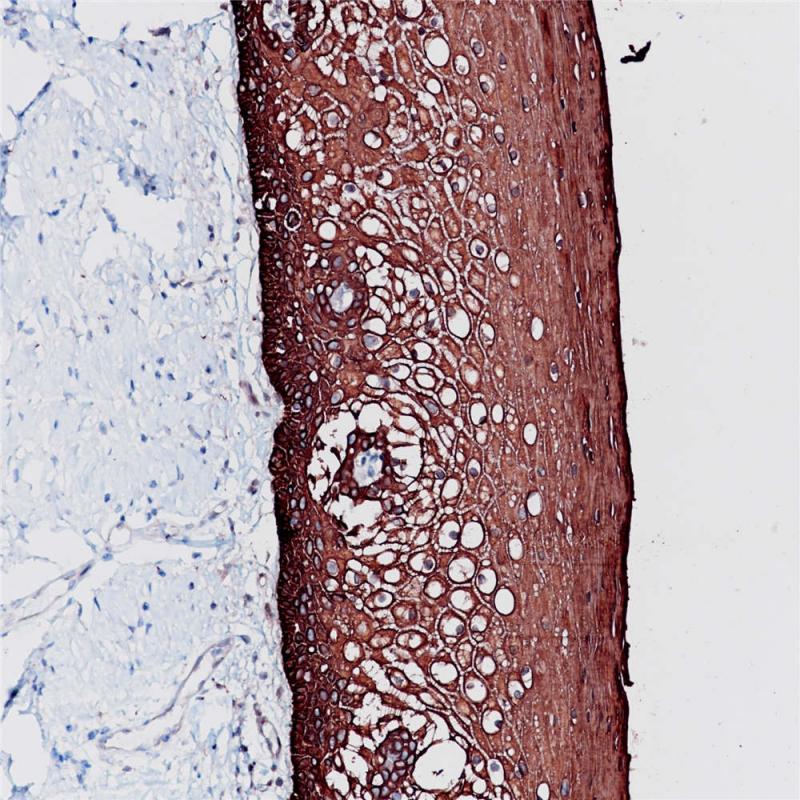

CK6是一种上皮特异性的I型角蛋白,通常与创伤后的角质细胞活化相关,因此也被认为是一类愈合因子,但是其与角质细胞的增殖以及转移无关。这个蛋白总是与I型角蛋白CK16成对出现。CK6通常在尚未角质化的上皮组织的基底层细胞中表达,在毛囊外根鞘中也有明显表达。在肿瘤组织中,CK6在多数的鳞状上皮癌中表达,特别是在鳞癌癌巢的中间成熟细胞层。CK6通常与CK5一起配套用于间皮瘤的鉴别诊断。

阳性对照

食管癌